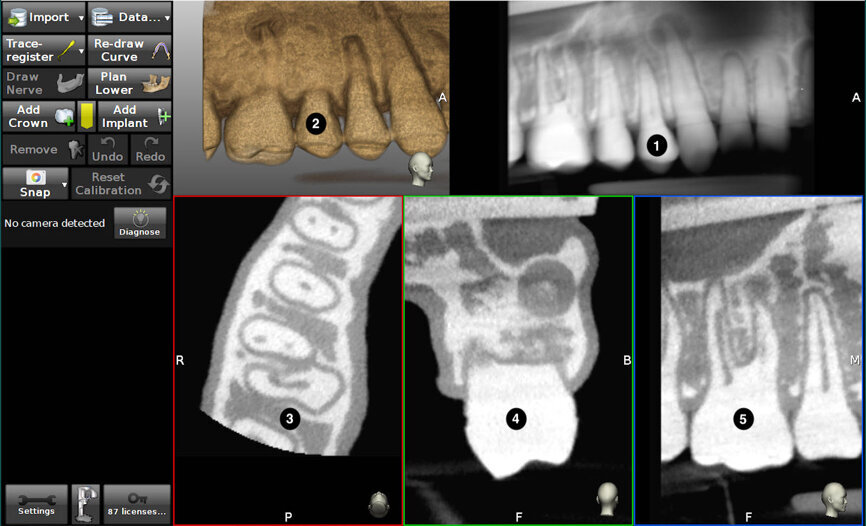

Fig. 3: The screen is divided into (1) panoramic view, (2) 3D reconstruction, (3) axial view, and (4) buccolingual and (5) mesiodistal section views.

The first stage of TaP workflow is the importation of the patient’s CBCT data set (as DICOM file) into the dynamic navigation planning software to reveal the dentition. The screen shows the streaming video, panoramic view, target view, depth indicator, and buccolingual and mesiodistal section views (Fig. 3). The access point of entry, the axis orientation/angulation and the depth of the access cavity are planned. For microsurgical procedures, the Piezotome pathway is based on the dimensions of the osseous pathology surrounding the root apex (Figs. 4a–c). The planning stage can be done at any time prior to the procedure, provided the CBCT scan is consistent with the current dentate condition. As a preliminary step prior to the trace registration, three to six trace starting points (landmarks) are chosen and marked on visible and accessible teeth. When the computer mouse is positioned over the 3D model, a 2D cross-sectional view appears. The red crosshair sticks to the landmark, its centre on the surface (Fig. 5). The software advises the clinician if it suspects that the landmark is in an incorrect position.